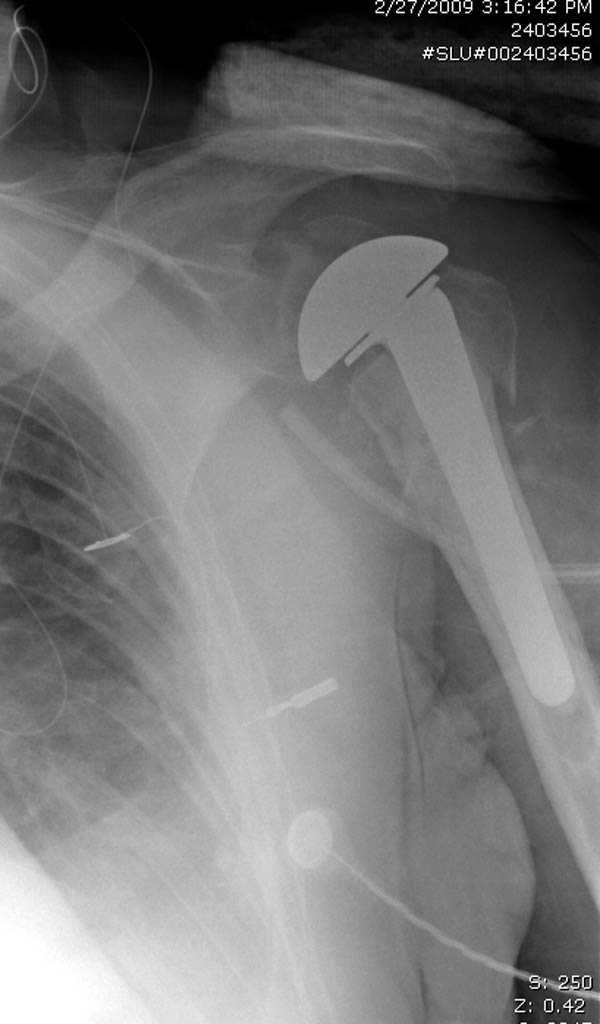

После устранения смещения пластина установлена выше (5,6,7) и финальные снимки (8,9,10)

дополнительные снимки по протезированию